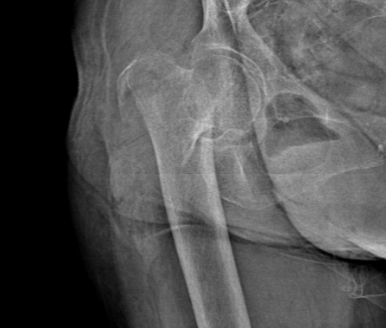

据了解,李奶奶于2021年7月8日在家不慎摔倒,导致右侧髋部疼痛、活动受限。经家人介绍,来到谢桥医院就诊。现场判断为“右侧股骨粗隆间骨折”,加之考虑到患者年龄、骨质等情况,立即被安排入院治疗。后经手术修复,2021年7月19日康复出院。

这次李奶奶在家中不慎摔倒,伤至右大腿,因语言功能障碍,未能及时被家人发现。次日在被家人发现其右大腿肿胀后, 2023年8月14日再次送至谢桥医院骨科进行治疗。经检查,诊断为“右股骨干骨折”。

入院后,谢桥医院骨科团队一边为李奶奶完善相关检查等治疗,一边进行多学科会诊紧急讨论。考虑到李奶奶是高龄骨折,同时在此之前已经进行过一次关节置换,针对这些手术难点,以及术中可能出现的突发情况,术前谢桥医院骨科团队经过反复讨论,并与其家属沟通后,最终确定了严密的手术计划和全面的治疗方案,决定为李奶奶施行“右侧股骨干骨折切开复位内固定术”。目的便是为了提高术后康复效果,极大程度减少并发症。